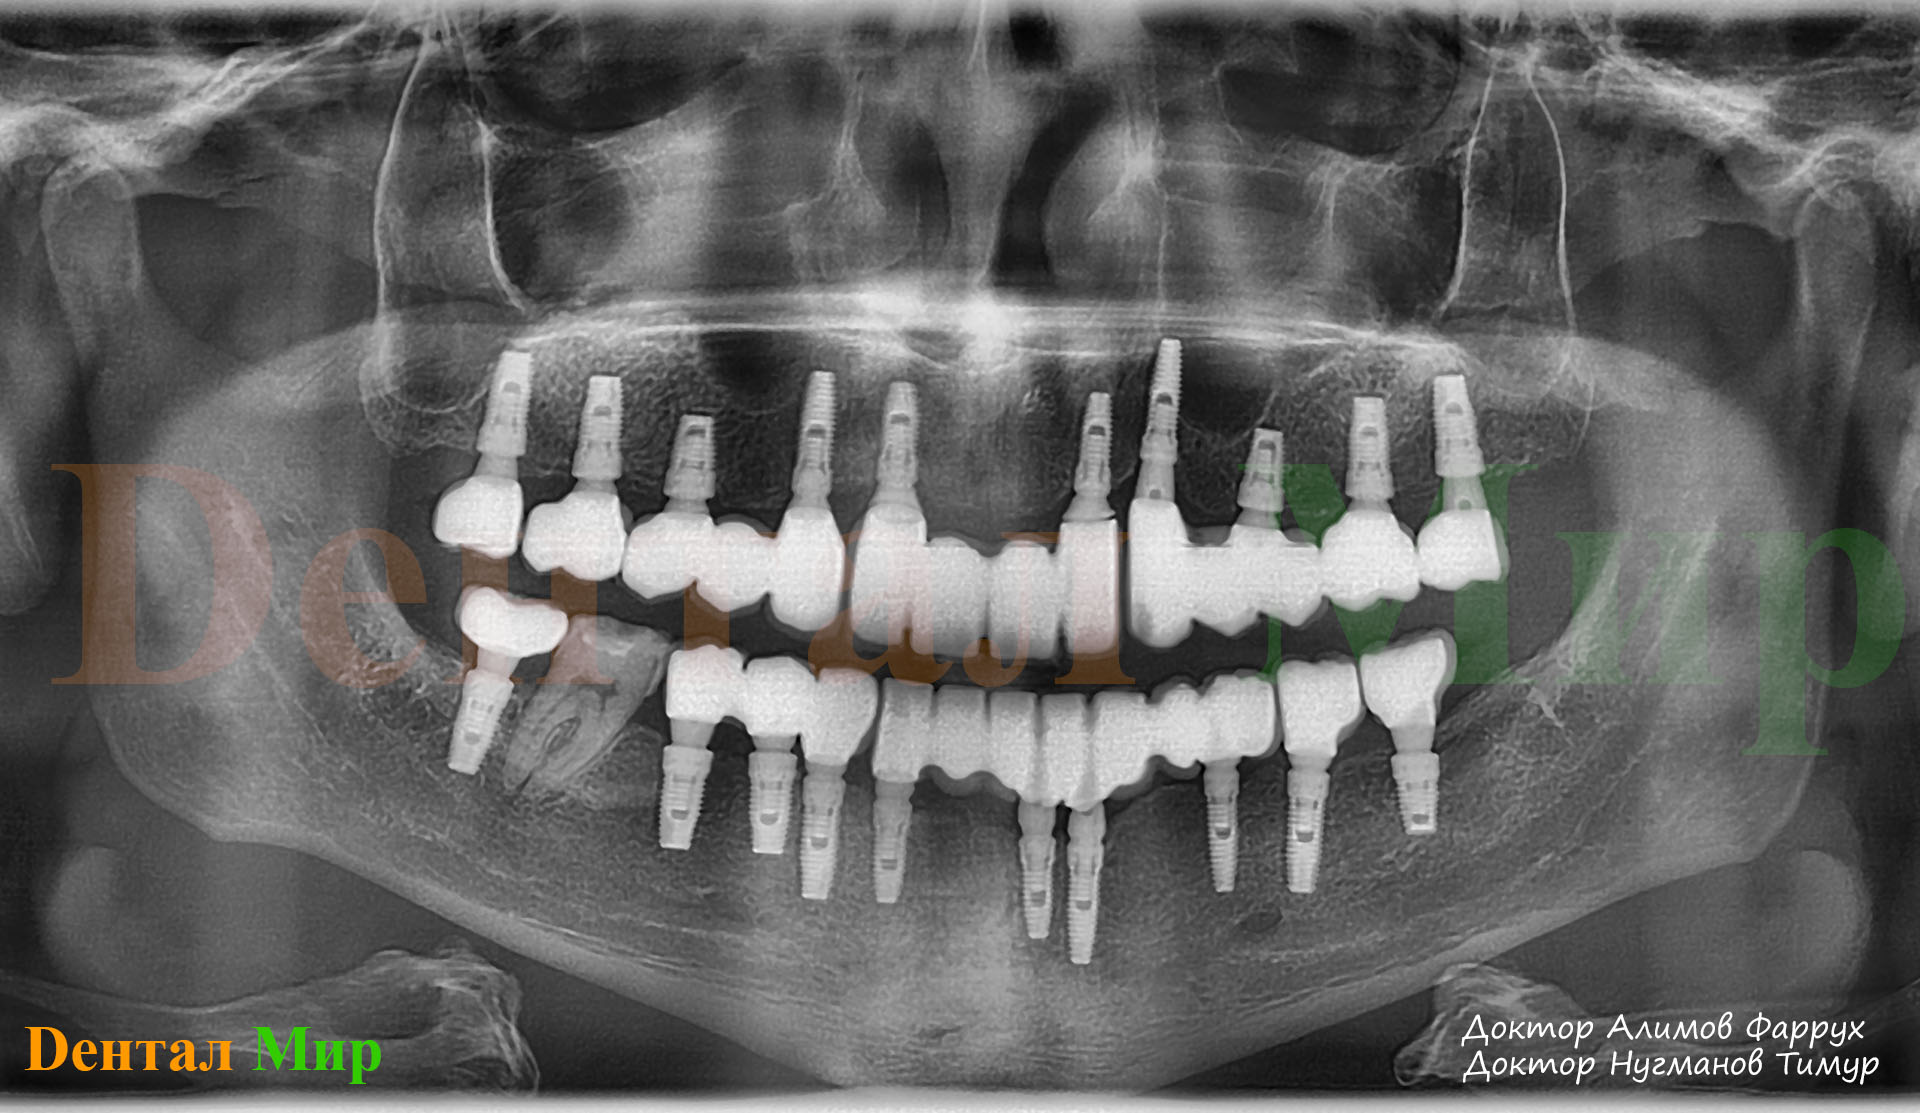

Рентген имплантов Alpha Bio: диагностика и качество